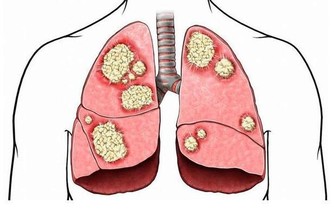

腎陽虛——畏寒怕冷為主要特徵。腎陽虛,會表現出腰部和膝關節酸軟或疼痛,而且發冷,怕冷四肢發涼,下肢尤其嚴重,面色白而沒有光澤或黑而晦暗,神疲乏力,精神萎靡,頭暈目眩;小便清長,夜尿增多,排尿無力,尿後餘瀝不盡,或尿少浮腫;或者肚子脹,容易拉肚子,拉的大便稀而且有不消化的食物,有的人表現為每天黎明時拉肚子;或性慾減退,男子陽痿早洩,遺精滑精;女子宮寒不孕,帶下清稀量多。

腎陰虛——上火為主要特徵。我們將腎陰虛的人稱為“燥熱一族”,他們在腎虛的同時有熱的徵象。腎陰虛體質的人,會出現腰部或膝關節酸軟疼痛,頭暈目眩、耳鳴耳聾、失眠多夢、形體消瘦;兩手心、腳心和心口發熱,身體像潮水一樣一陣一陣的發熱,夜裡睡覺時出汗(盜汗),面紅顴赤,口乾咽燥,大便乾結,小便短少色黃;男子陽強易舉(陰莖容易勃起),遺精早洩;女子月經量少,甚至閉經,或月經淋漓不盡等表現。